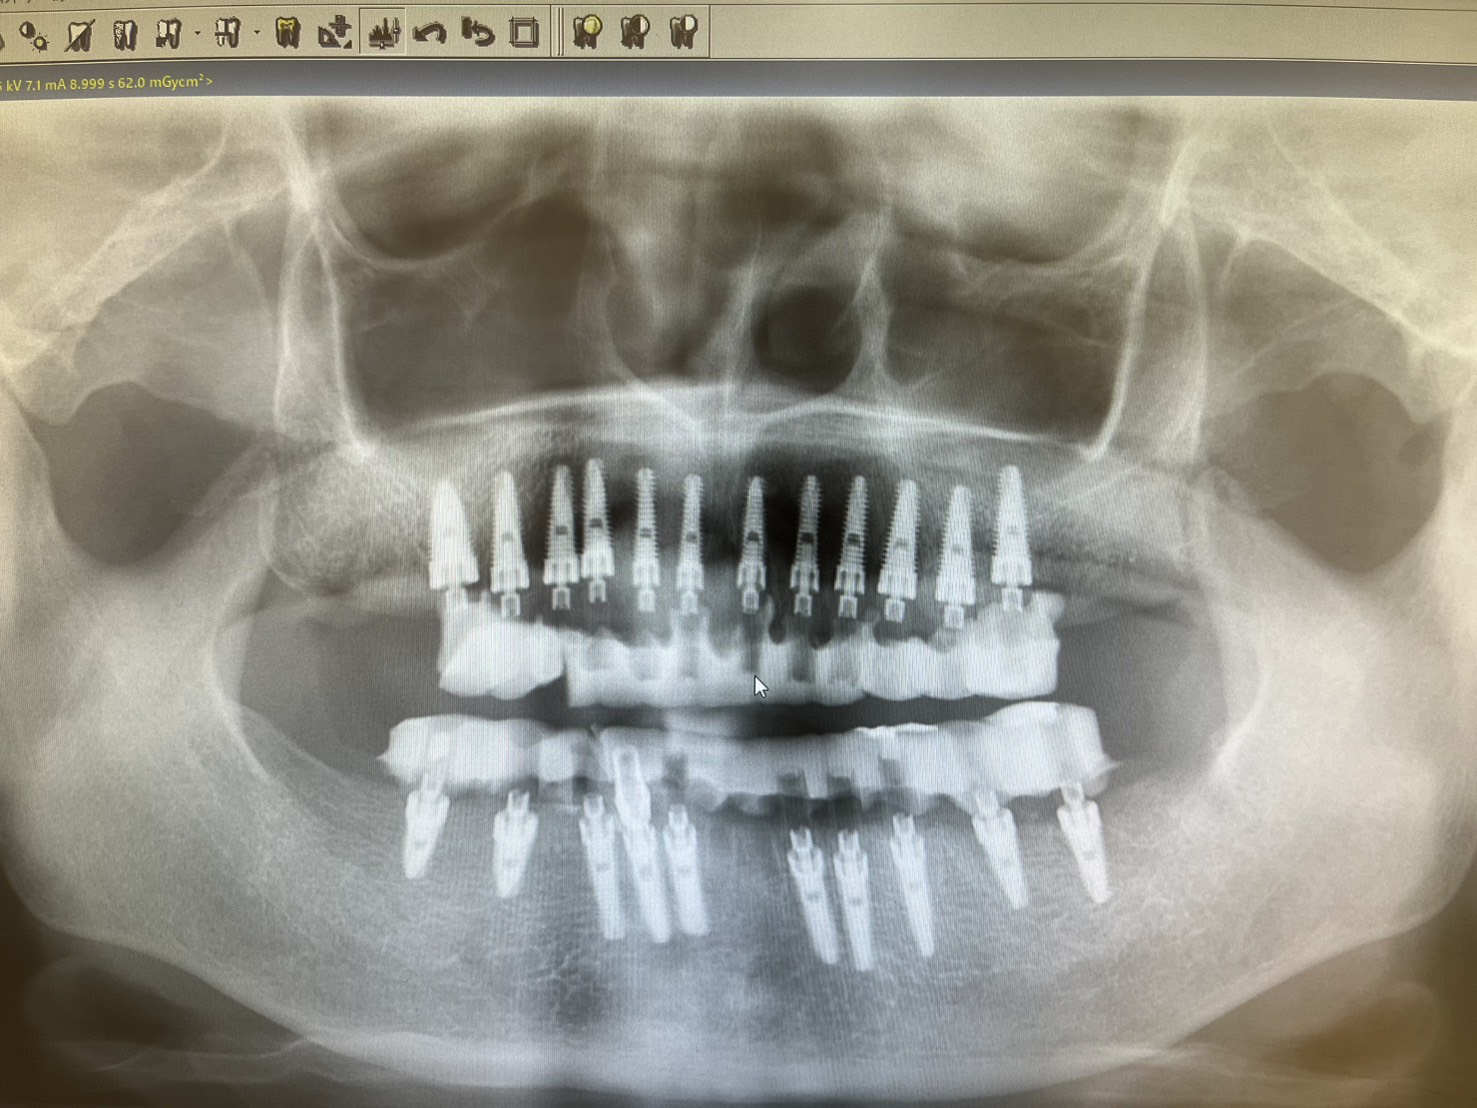

一位患者特地從外州飛到拉斯維加斯,評估後當天決定進行全口植牙。整個療程不到兩小時,即拔即植即固定臨時牙。

手術當天完成全口掃描,四個月後更換為最終固定假牙。這段期間,患者維持良好的生活品質,醫師也能安心照護,不用每天提心吊膽、接不完病患來電。

不需要全身麻醉,或者是舒眠麻醉的情況之下,就完成與自然牙排列相仿全口重建。不用擔心歪斜長長的植體打到顴骨或眼睛。